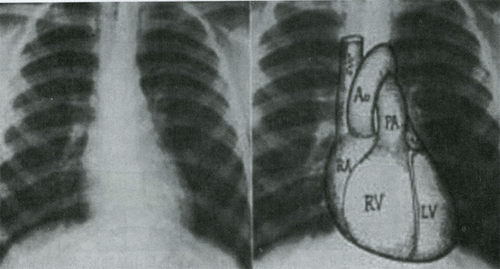

一、正常心脏大血管X线表现

三、左心室增大

1.心尖向下向左延伸。

2.心腰凹陷。

3.主动脉结突出。

4.心影呈靴形。